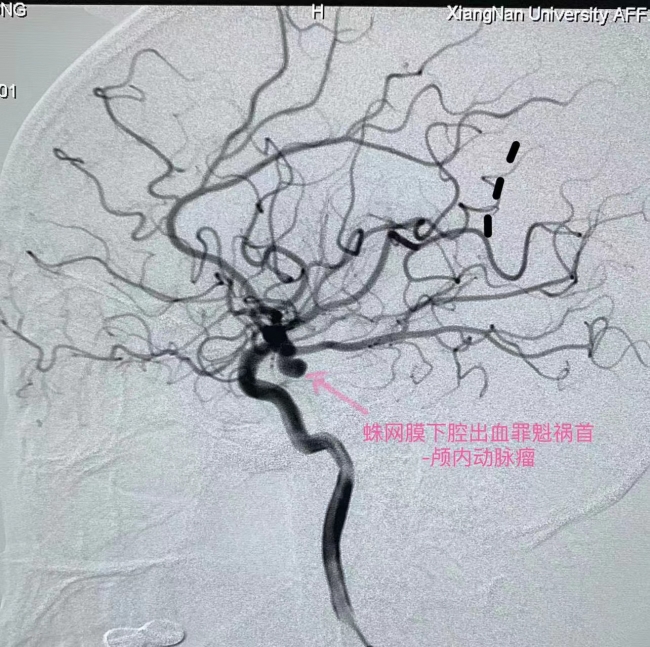

3月11日晚上10点多,彭女士正与家人相聚聊天、打牌,突然感觉到一阵剧烈头痛,就失去意识、陷入昏迷。家人紧急拨打120,将她送往湘南学院附属医院就诊。急诊CT+CTA检查显示,彭女士是蛛网膜下腔出血,颅内有一个4.3*5.8mm大小的形态不规则的动脉瘤,动脉瘤的破裂导致了蛛网膜下腔出血。

“蛛网膜下腔出血是最凶险的脑血管疾病之一,发病时感觉头要爆炸了,所以称其为一生中最厉害的头痛。第一次出血死亡率大约为30%,再次出血死亡率可达60%-70%以上。蛛网膜下腔出血有八成左右是由于颅内动脉瘤破裂所致,故颅内动脉瘤也被形象地比喻为颅内不定时炸弹。”湘南学院附属医院神经介入治疗组组长、神经内二科副主任医师龙亮介绍,“就像汽车的车胎用久了,会形成一个鼓包,不去修补它,就会爆胎。脑血管上也会在高血压、脑动脉硬化、感染炎症、血管自身发育不良等因素作用下形成薄壁鼓包,受血流冲击或者在情绪激动情况下,导致破裂致蛛网膜下腔出血。”

时间就是生命!接诊后,我院神经内二科、急诊科、放射科等立即启动急诊绿色通道,在最短的时间内完成了相关检查,并为彭女士进行了神经介入手术——经导管颅内动脉瘤弹簧圈栓塞术。